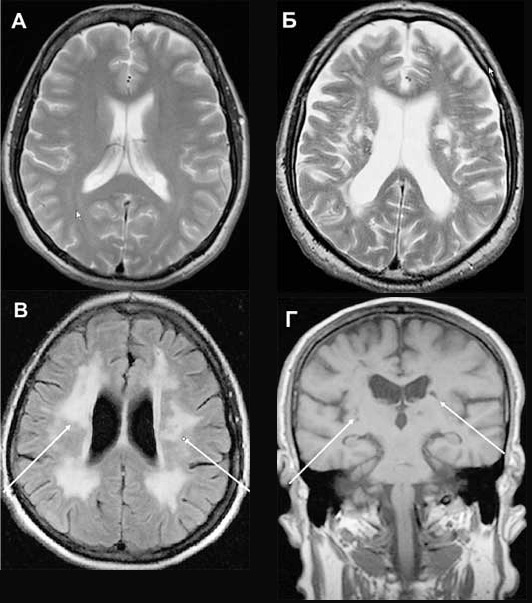

При болезни Бинсвангера из-за утолщения стенок и сужения просвета мелких артерий возникает диффузное поражение внутренних структур мозга — так называемого белого вещества. Множественные мелкие очаги поражения представляют собой участки отмерших нейронов. У больных происходит нарушение циркадных (суточных) колебаний давления: в ночное время оно или падает слишком резко, или, наоборот, повышается, хотя давление ночью должно незначительно снижаться. Один из основных симптомов болезни — нарушение сна. Больной плохо засыпает или спит с частыми пробуждениями. Другие типичные признаки — медленное прогрессирование нарушений памяти и интеллекта вплоть до деменции (слабоумия); нарастающие нарушения походки, расстройства мочеиспускания и дефекации. Известно, что болезнь Бинсвангера может настичь даже в относительно молодом возрасте — до 35 лет.

Для другого вида дисциркуляторной энцефалопатии — так называемых мультиинфарктных состояний — характерны множественные небольшие инфаркты в мозге (микроинсульты). Это означает, что на определенном участке мозга из-за закупоривания сосуда происходит омертвление нервной ткани. При этом поражаются как поверхностные (серое вещество), так и глубокие (белое вещество) структуры мозга.

Настоящую революцию в исследованиях мозга произвело появление метода компьютерной томографии, сочетающего достижения рентгенографии и компьютерных методов обработки данных. С его помощью можно получить не косвенные, а прямые данные о структурах мозга и их изменениях. Метод позволяет определить расположение и размеры очагов поражения мозга и их характер.

В последнее время для диагностики нарушения кровообращения мозга применяют магнитно-резонансные методы: ядерный магнитный резонанс, магнитно-резонансную томографию и магнитно-резонансную ангиографию. Ядерный магнитный резонанс дает информацию о физико-химических свойствах структур мозга, благодаря чему можно отличить здоровые ткани от измененных. Магнитно-резонансная томография позволяет получить изображения мозга, определить расположение, размеры, форму и количество очагов, изучить мозговой кровоток. Магнитно-резонансная ангиография представляет собой модификацию магнитно-резонансной томографии. С ее помощью можно исследовать прохождение и «калибр» внечерепных и внутричерепных артерий и вен.